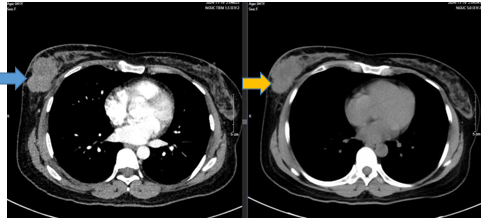

- CT ngực trước điều trị:

Hình 2: Vú phải vị trí 1/2 dưới có khối tổn thương ~50x34mm, thâm nhiễm xung quanh, xâm lấn gây dày da vú lân cận. Hố nách trái có vài hạch đường kính ngắn 9mm, vỏ dày 7mm, ngấm thuốc mạnh sau tiêm.

Hình 3:

Trước điều trị khối u vú phải ~70x59x37mm (mũi tên xanh), xâm lấn da ~34mm. Hạch thuộc chặng 1lớn nhất ~9x14mm, hạch chặng 2 ~5mm. Sau điều trị u vú phải ~16x23x36mm (sau điều trị mũi tên vàng), tổn thương xâm lấn da ~ 25mmHố nách bên phải chặng I có vài hach, còn rốn hạch vỏ hạch dày, lớn nhất ~ 4x6mm.